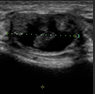

胸部自体脂肪移植前后 超声波

颜美整形医院为了确保术前状态及与术后无副作用,为患者提供术前术后超声波检查.